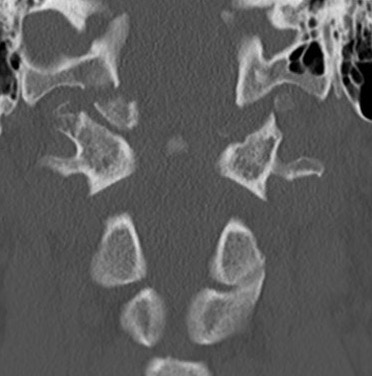

Xray / CT measurements

Frequently missed on xray

Power Ratio BC/AO > 1

- basion to posterior arch / opisthion to anterior arch